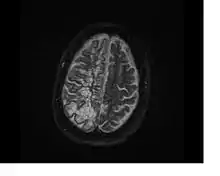

In humans, perivascular spaces surround arteries and veins can usually be seen as areas of dilatation on MRI images. While many normal brains will show a few dilated spaces, an increase in these spaces may correlate with the incidence of several neurodegenerative diseases, making the spaces a topic of research.[4]

Perivascular spaces are most commonly located in the basal ganglia and white matter of the cerebrum, and along the optic tract.[13] The ideal method used to visualize perivascular spaces is T2-weighted MRI. The MR images of other neurological disorders can be similar to those of the dilated spaces. These disorders are:[7]

Perivascular spaces are distinguished on an MRI by several key features. The spaces appear as distinct round or oval entities with a signal intensity visually equivalent to that of cerebrospinal fluid in the subarachnoid space.[7][14][15] In addition, a perivascular space has no mass effect and is located along the blood vessel around which it forms.[14]